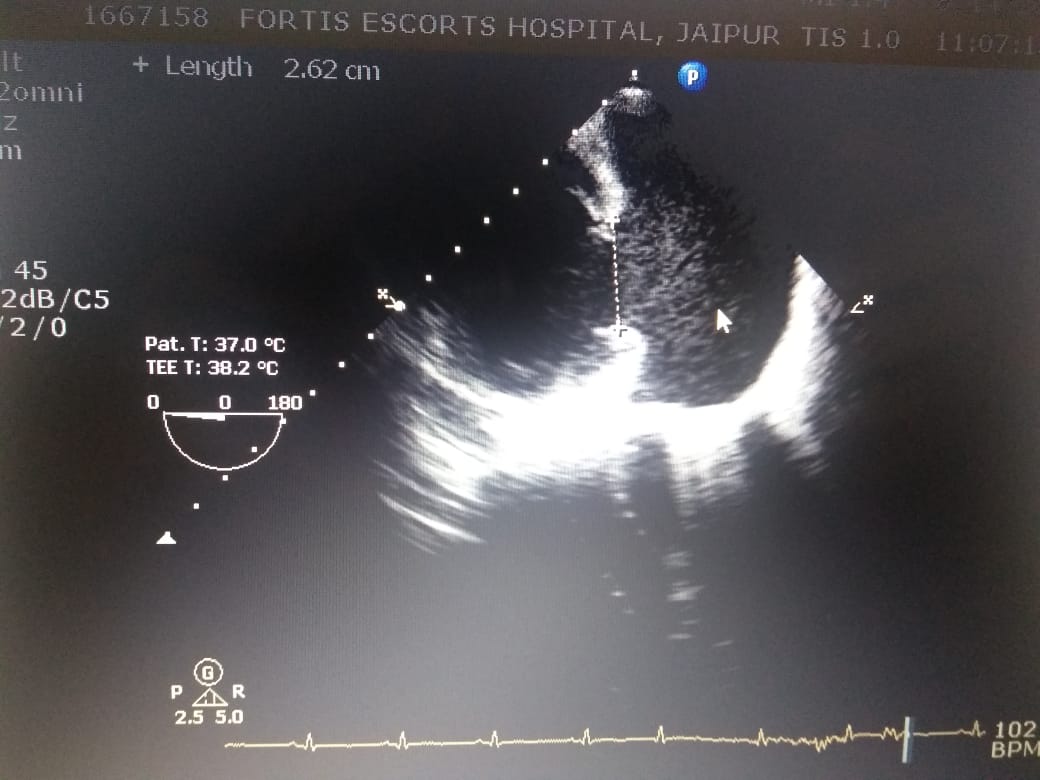

The patient, a known case of CAD & post PTCA, presented with acute limb ischaemia due to thrombus at

aortic bifurcation. On further investigation he was found to have CONTAINED RUPTURE OF LEFT

VENTRICLE WITH LARGE COMMUNICATING PSEUDOANEURYSM WITH CLOTS.